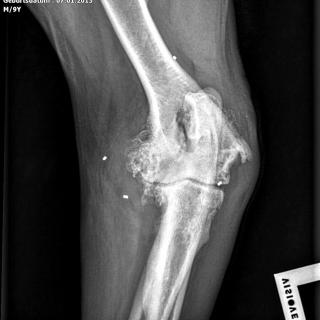

Die Möglichkeiten der Tiermedizin entwickeln sich ständig weiter und ermöglichen eine stetige Verbesserung der Diagnostik und der Effektivität der Behandlung auch bei schwerwiegenden Erkrankungen. Zentraler Bestandteil und Ausgangspunkt einer zielgerichteten Diagnostik und Therapie ist eine moderne und umfassende Ausstattung im Bereich der Bildgebung und entsprechend qualifizierte Mitarbeiter. In unserer Praxis können wir unter anderem folgende radiologische Verfahren zum Wohle unserer Patienten einsetzen: